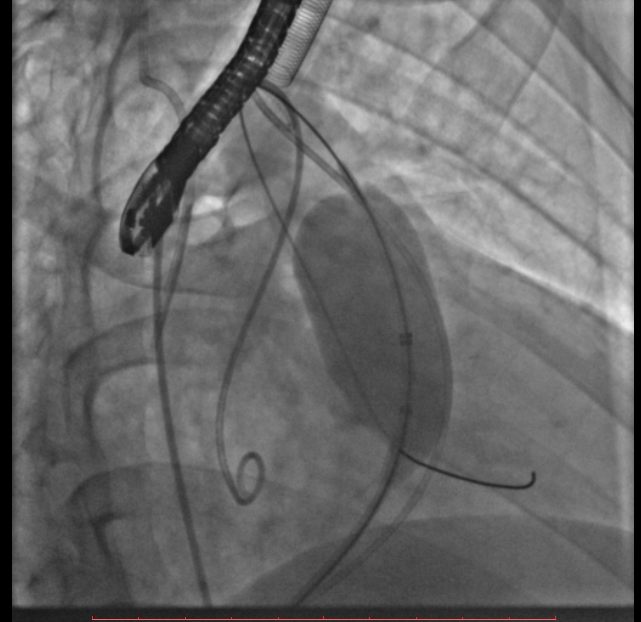

术中测量患者基础主动脉、肺动脉、右心室压力分别为111/58mmHg、31/4/13mmHg、34/1/6mmHg,通过肺动脉造影,术中测量球囊内径为32mm(见图二),选择36-25mm VENUS-P肺动脉瓣膜,在肺动脉造影指引下逐步打开瓣膜。考虑到患者肺动脉分叉较短,存在瓣膜释放后移位风险,故选择高位释放法(图三)。但释放瓣膜后造影提示右肺动脉开口局部被阻挡(图四),复测患者主肺动脉、左肺动脉、右肺动脉压力分别为57/13/25mmHg、55/12/24mmHg、27/7/14mmHg。

图二:术中扩张球囊刚好堵住右室流出道,测量球囊内经为32mm